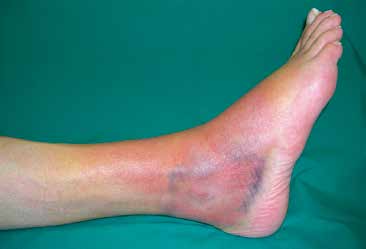

Als nächster Schritt sollte dann eine eingehende klinische Untersuchung durchgeführt werden. Man beginnt mit der Inspektion, wobei Lokalisation und Ausdehnung von Schwellung und Hämatomverfärbung erfasst werden (Abb. 1).